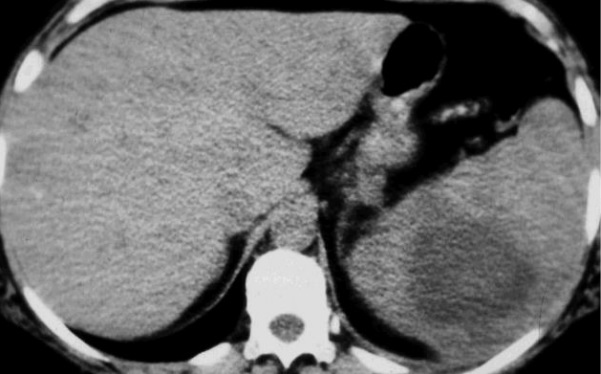

. Aspect radiologique TDM est une collection hypodense peut

en cloisonne , sa paroie se rehaussement apres injection de

contrast intra veineux .et souvent se presenter des bulbe

gaz

Aspect radiologique TDM d/une abces

a pyogene de la rate est une lesion arrondie a

hypodensite , sa parois etre epaisse et cloisonee et

se rehaussement apres injection de contrast

intraveineux |